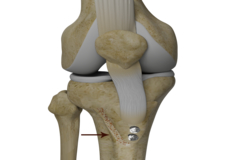

Bone-Patellar Tendon-Bone (BPTB) Autograft

ACL reconstruction with BPTP autograft is a surgical procedure that replaces the injured ACL with an autograft containing patellar tendon and bony attachments. The new ACL is harvested from the patellar tendon that connects the bottom of the kneecap (patella) to the top of the shinbone (tibia).

Bone-Patellar Tendon-Bone (BPTB) Allograft

ACL reconstruction with BPTP allograft is a surgical procedure that replaces the injured ACL with an allograft containing patellar tendon and bony attachments. The goal of the surgery is to tighten your knee and to restore its stability.